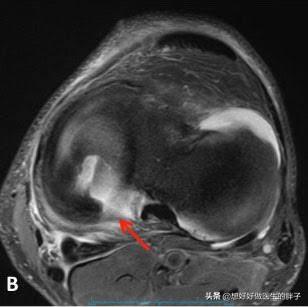

那么如果出现了这种症状,我们需要的不是怎么样护理,而是首先要明确病因,要知道关节内的半月板以及关节软骨是否发生了损伤?这样我们就必须要进行膝关节核磁检查明确关节内的具体情况。

如果核磁显示半月板整体的形态还算良好,那么我们完全可以采取休息以及康复锻炼等办法帮助患者缓解症状,而如果半月板整体的形态有了明显的改变,那么说明半月板发生了三度撕裂,这种情况一般要进行关节镜手术治疗,才能帮助患者解决问题。